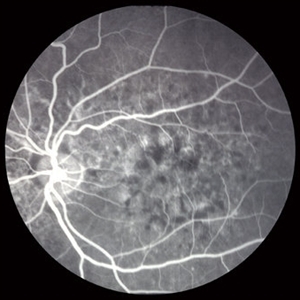

Deferoxamine retinopathy slide 4

Changes on flourescein angiography were relatively symmetric and involved the posterior pole.

Deferoxamine Retinopathy slide 3

Flourescein angiography revealed wide spread disturbance of the retinal pigment epithelium with hypo and hyper flourescence. Angioid streaks are also present.